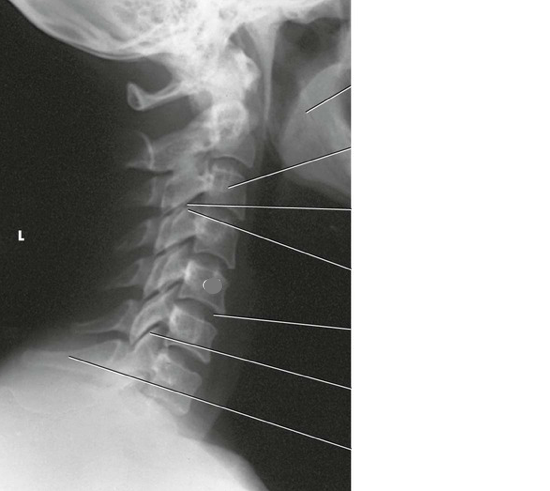

Question 2

Question

Label the image

Image:

6f372c5e-5005-4f0f-ba2b-b7f38f13a390 (image/png)

Answer

C4

occipital bone

intervertebral disk space

spinous process

C7